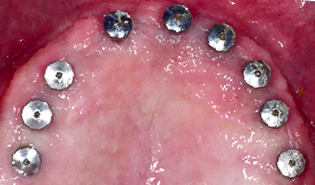

3.2 Immediate Load Prosthetics (All-on-4)

This part of the course covers the methods of diagnosis, practical treatment planning, pre-surgical prosthodontics, imaging, armamentarium, and clinical techniques needed for this exciting treatment modality. Crucial to this treatment modality is the understanding of the biomechanical aspects and functional loading of the immediate full arch prostheses. The aesthetic and phonetic requirements, space requirements, laboratory communication, insertion techniques post-operative follow-up and hygiene requirements are key to this treatment.

Tilted implants - biomechanical aspects and survival rates

Cantilevers

Establish a systematic and organised approach to the prosthetic techniques for this modality of treatment

Complete sequential treatment planning from patient examination to post insertion follow up and protocols

Explain the anatomical maxillary and mandibular considerations and limitations in relation to immediate load of full arches